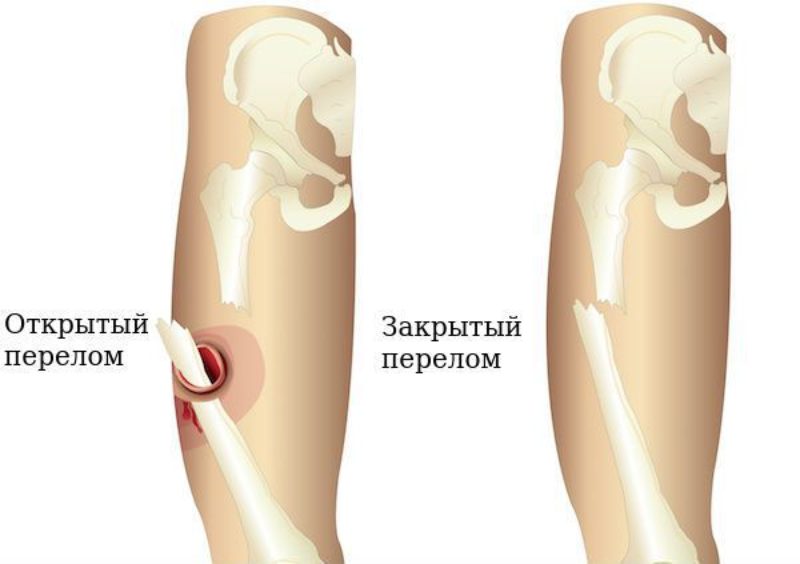

Мультяшные сломанные кости: Рисунки и комиксы

Раздел: Фотоархив